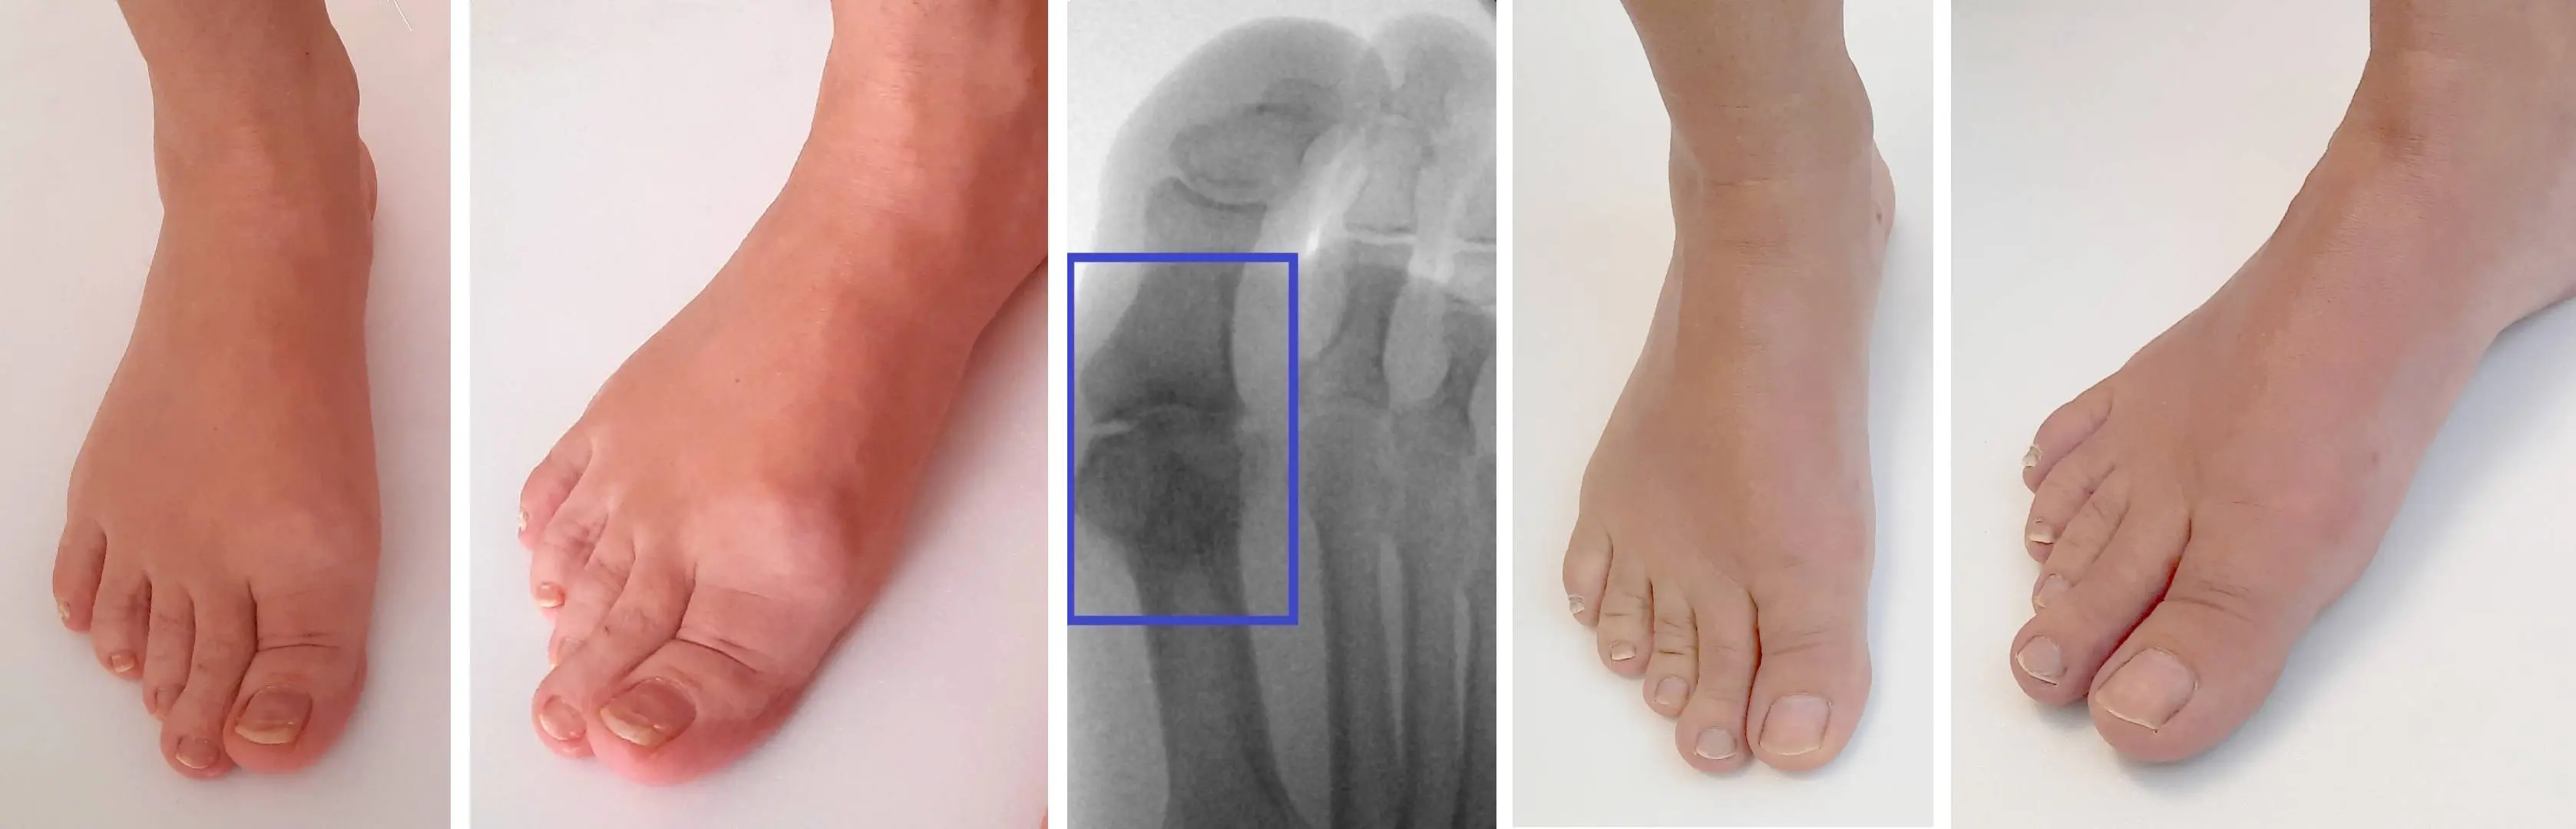

Obrázky: Vlevo předoperační snímky. Lze vidět zduření kloubu způsobené kostními výrůstky. Stav je provázený bolestí při chůzi, kulháním a omezením hybnosti. Uprostřed na rentgenovém snímku jsou patrné mírnější artrotické změny, kostní výrůstky a úbytek chrupavky kloubu. Vpravo pooperační fotky 4 měsíce po operaci. Kostní výrůstky jsou odstraněny a obnovena hybnost v kloubu. Pooperačně téměř neznatelná jizva na vnitřní straně palce.